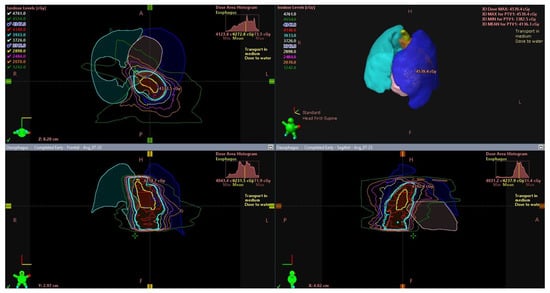

2.1. Intraductal Brachytherapy as an Independent Treatment in Early Esophageal Cancer

2.2. Brachytherapy Combined with Teleradiotherapy in the Treatment of Early Esophageal Cancer